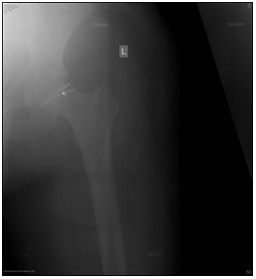

Five to seven days after the surgery supracondylar direct extension with traction of 10kg. Has resulted with an increase in range of motion. However this progress has happened after the withdrawal of pain. After three weeks direct extension was removed. Abduction brace and physiotherapy rehabilitation, there was no weight bearing. Weight bearing was possible three months postoperative. The patient was advised to continue follow up every six months to evaluate any progression of arthritis and the need for another operative treatment. Three years after surgery good clinical outcome has been noticed with painless and full range of hip joint motion. The patient if satisfied (Figure 6).

Figure 6 First postoperative image.